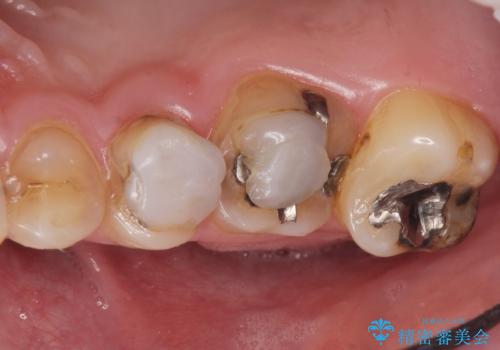

- K-POP(Kポップ)アイドルのような歯にしたいと希望され来院された患者様です。

矯正を途中でやめてしまったとのことで、歯に矯正の接着材が残っており着色も顕著でした。

奥歯の咬合面にはレジンが盛られた状態でした。

見た目と咬み合わせを改善するため、セラミッククラウンによる治療を行いました。